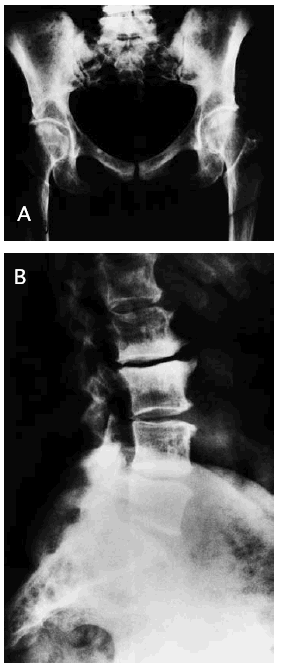

El resto del estudio radiológico óseo se apreciaba un aumento de la densidad ósea parcheada (fig. 2A y B) con deformidad tubular en la metáfisis de los huesos largos.

Fig. 2.